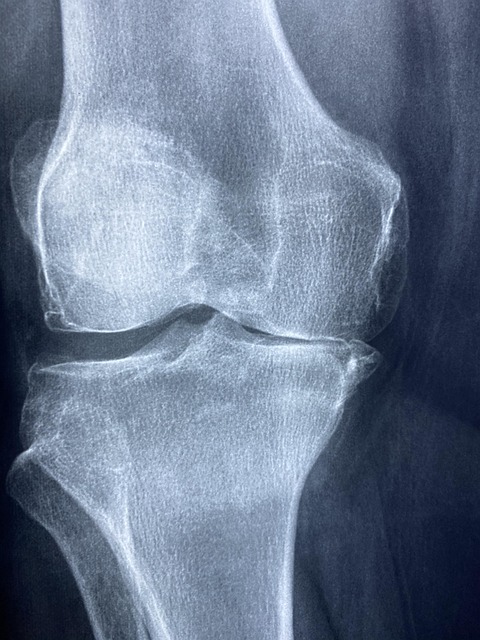

2-1. 관절 통증 완화

무릎·고관절 등 골관절염 환자 대상 연구에서 콘드로이친은 통증 감소 및 관절 기능 개선에 효과가 있음이 확인됐습니다. 특히 6개월 이상 장기 복용 시 NSAID와 유사하거나 더 나은 결과를 보였습니다.

2-2. 연골 보호 및 재생

콘드로이친은 연골 구성 요소(프로테오글리칸, 콜라겐, 히알루론산) 합성을 촉진하고, 연골 파괴를 촉진하는 엘라스타아제, 프로스타글란딘 E2, IL‑6, NF‑κB 등의 염증 경로를 억제합니다.

이에 따라 6~12개월 장기 섭취 시 연골 손실 속도가 감소하고, 관절 공간 유지에 도움이 되는 것으로 나타났습니다.